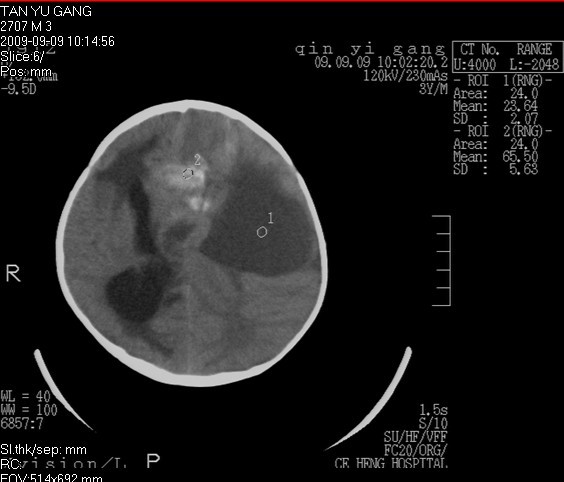

男  4岁  家长觉得反应迟钝来检查发现。

考虑脑占位并出血,脑疝形成。

考虑左侧颞顶叶占位并出血,脑疝形成

pnet?建议mri进一步检查。

有出血,考虑神经母细胞瘤或星形细胞瘤,胶母好发老年人,儿童罕见,中颅窝的是扩大的侧脑室颞角吧不是囊肿吧。脑白质密度减低,建议mr.

先天性疾病.小脑是正常的,左侧大脑半球发育不良伴有脑肿瘤形成,脑积水.名堂真多。建议mri

考虑左侧颞顶叶占位并出血,脑疝形成!梗阻性脑积水

考虑左侧颞顶叶占位并出血,脑疝形成,梗阻性脑积水。

1)考虑左侧额颞顶叶肿瘤并卒中;建议行进一步检查。2)大脑镰下疝,左侧颞叶沟回疝。3)脑积水(梗阻性)。